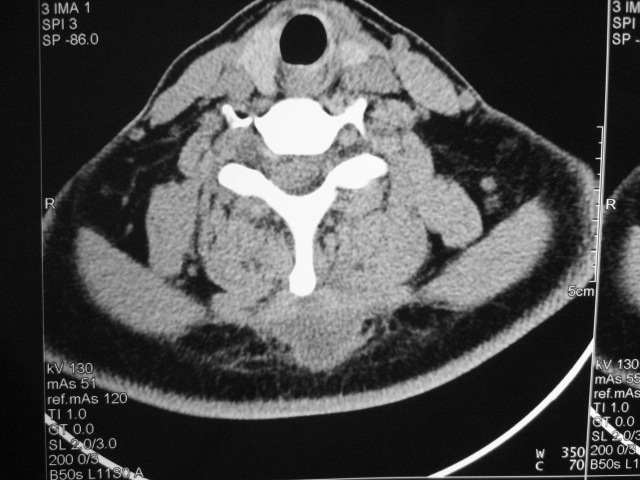

女,46岁,发现颈后区肿块3月余.

颈后软组织肿块,内可见坏死区及点状钙化,邻近颈椎棘突可见破坏,邻近肌间隙模糊,肿块周围脂肪间隙可见索条状影。

考虑:1)感染,结核可能;

2)肿瘤不能排除。